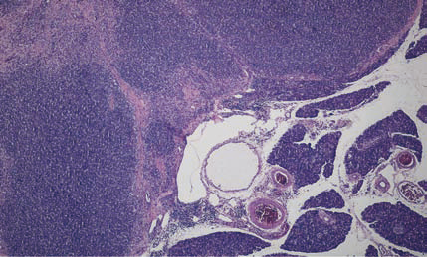

胰腺在多种至关重要的代谢功能中担负着重要的角色。胰腺外分泌部会分泌消化酶,在营养成分的利用过程中必不可少。胰腺外分泌部的炎症和退行性病变在犬猫也十分重要。